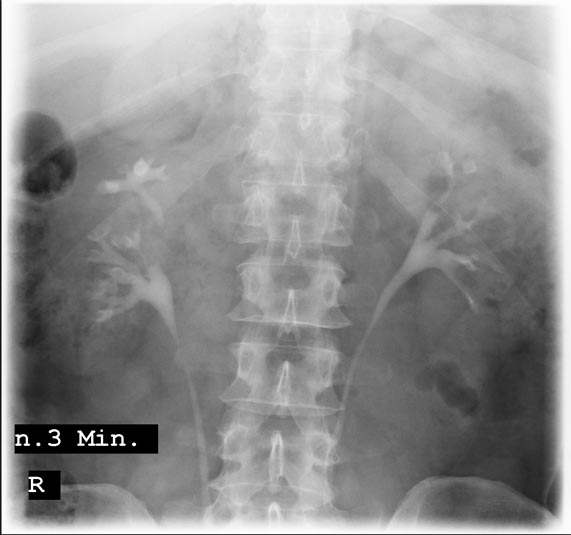

Ultraschalluntersuchung von Nieren und Blase